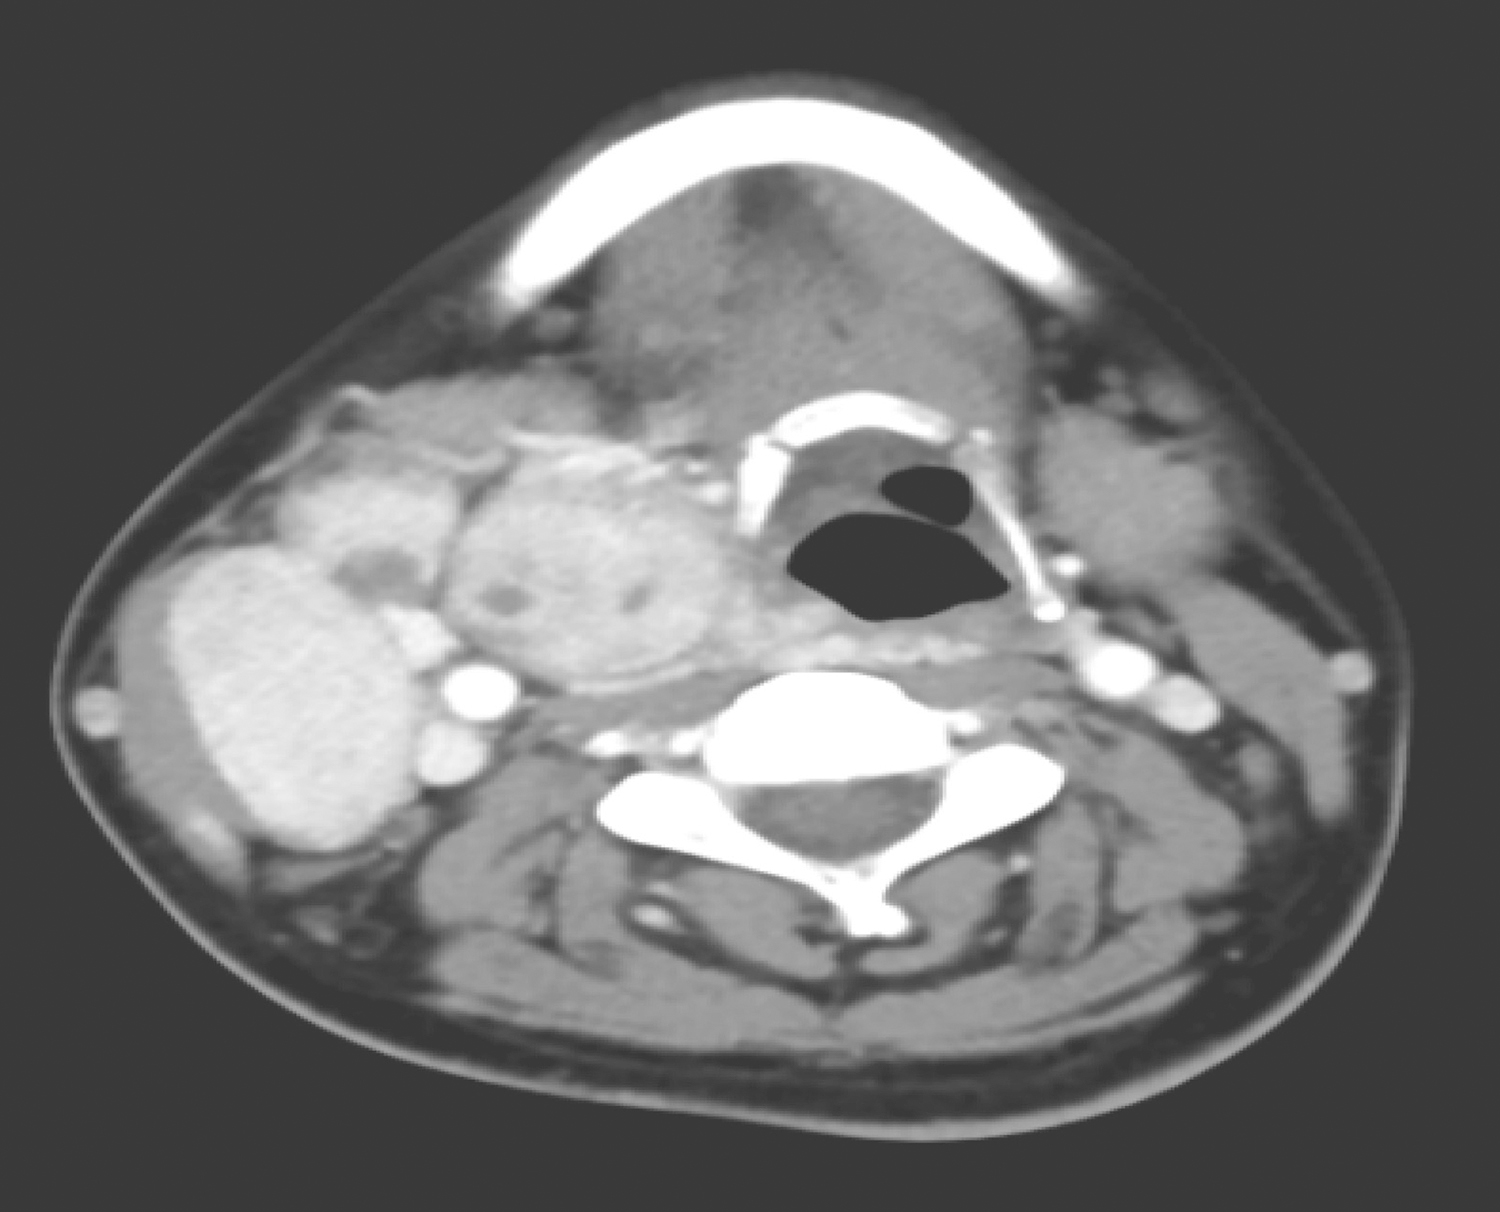

甲状腺弥漫不规则增大,密度不均匀,右叶为著,内有多发高、低密度结节影,大者最大截面约2.5cm×2.2cm,边界不清,增强扫描呈不均匀强化,向下伸入上纵隔胸骨后(图1);另见甲状腺左叶低密度结节,大小约1.6cm×1.0cm,不均匀轻中度强化。右侧颈部、锁骨水平及上纵隔区可见多发结节及肿物影,呈多结节融合状,最大截面约5.1cm×3.6cm,部分层面似与甲状腺右叶肿物相连续,包绕右侧颈动脉鞘,压迫右侧舌骨及下咽腔,增强扫描呈明显强化(图2)。双肺可见多发结节影,大者约1.9cm×1.4cm,边界清楚,明显强化(图3)。

图1 颈部增强CT示甲状腺右叶低密度结节